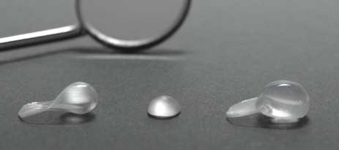

Osmotický hydrogelový expander měkkých tkání